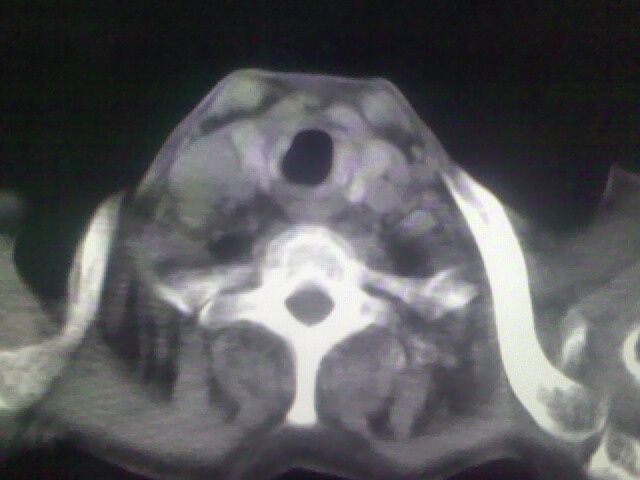

1)考虑右肺上叶周围型肺癌并纵隔及右颈部淋巴结转移,肝脏多发性转移。2)肺气肿。3)冠状动脉及主动脉钙化。

1)考虑右肺上叶周围型肺癌并纵隔及右颈部淋巴结转移,肝脏多发性转移。2)肺气肿。3)冠状动脉及主动脉钙化。支持!另:胃内病变不好确定,建议行胃镜!

1、右肺上叶周围型肺癌并纵隔、颈部淋巴结转移,肝多发转移灶。

2、胃充盈欠佳,不能确定。